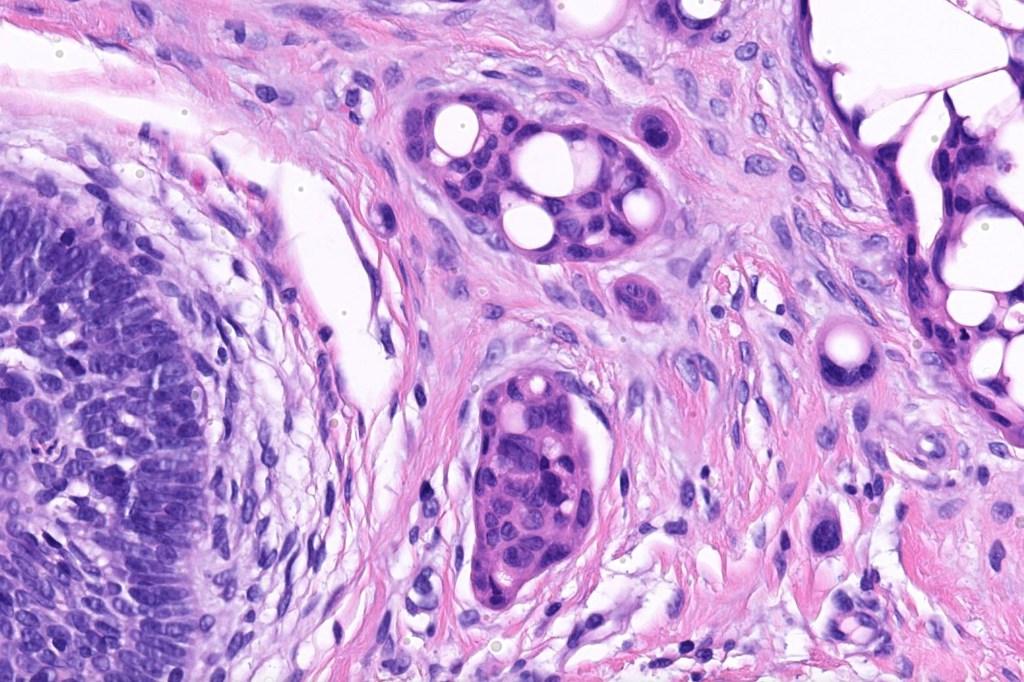

Histological features

•Generally circumscribed nodules/cysts

•Interconnecting epithelial strands giving rise to the cribriform growth pattern

•Ductal differentiation

•Hyperchromatic nuclei with variable pleomorphism

•Mitoses sparse or absent

•Focal decapitation secretion and presence of more typical apocrine carcinoma-like nests